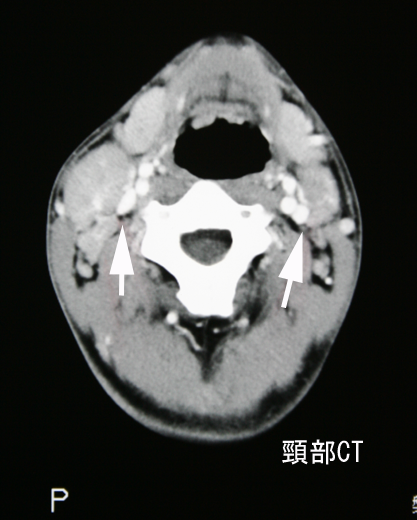

画像所見

CT所見:両側上内深頸リンパ節腫大が認められる。右副神経リンパ節も対側に比較して大きい。リンパ節腫大の内部は均一である。(クリックで大きい画像が見られます)